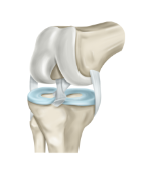

무릎 인공관절 수술비용 수술 후 회복기간 등 무릎 인공관절과 관련된 정보를 알아보도록 하겠습니다. 무릎 인공관절 수술은 무릎 관절의 연골이 마모되어 통증이나 퇴행성 관절염 등의 증상이 심해진 경우에 시행하는 수술입니다. 무릎 관절의 손상된 부분을 인공적으로 만든 금속이나 플라스틱 재료로 대체하는 것이죠. 이렇게 하면 무릎의 움직임이 원활해지고 통증이 줄어들게 됩니다.

무릎 인공관절이란 무릎 관절의 연골이나 뼈가 심하게 손상되어 통증이나 기능장애가 있는 환자들에게 수술적으로 삽입하는 인공적인 관절입니다. 무릎 인공관절은 금속과 플라스틱으로 만들어져 있으며, 마모된 무릎 관절의 일부나 전체를 대체합니다.